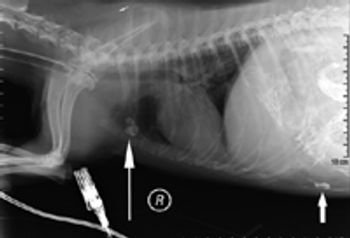

A 2-year-old intact male Boston terrier was evaluated because of a recent onset of gagging and vomiting.

Are contrast studies still needed as diagnostics in vomiting patients?